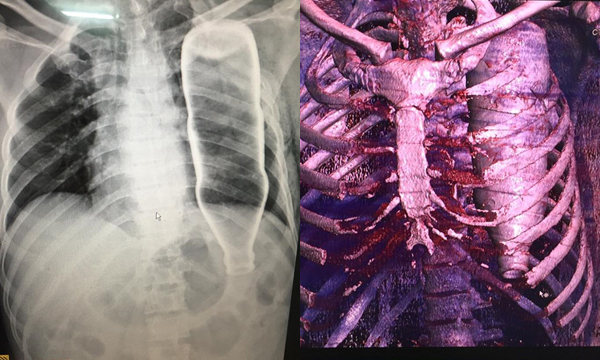

Ngã cầu thang, vỏ chai chui tọt lồng ngực

Ngày 28/5, BV Đà Nẵng tiếp nhận một ca cấp cứu vô cùng hy hữu. Bệnh nhân N.H.B (53 tuổi, Quảng Nam) chuyển đến BV trong tình trạng hoảng loạn, khó thở, đau tức ở vùng ngực do bị ngã cầu thang.

Theo lời người nhà, trong lúc vấp ngã, ông B. bị một vật chui vào nhưng không rõ vật gì. Kết quả chụp X-quang và CT khiến tất thảy BS ngỡ ngàng khi nằm trọn trong lồng ngực bệnh nhân là vỏ chai to như như chai nước khoáng, gây gãy 2 xương sườn, lõm xương đòn. Sau phẫu thuật, dị vật được lấy ra là chai đựng nước thuỷ tinh.